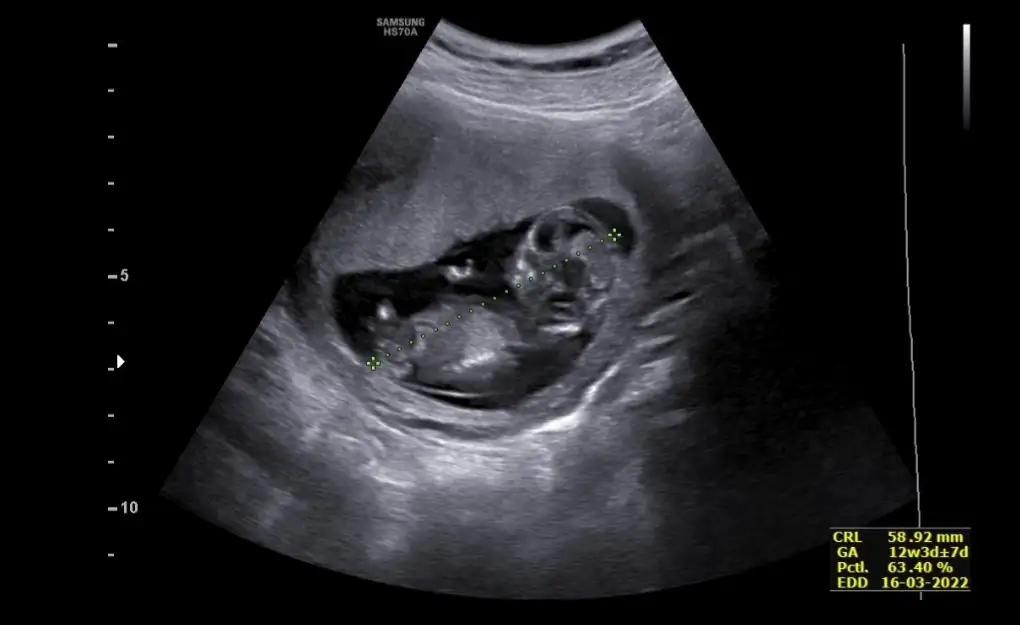

Merhaba bana da tahmin yapabilir misiniz?Erkek ve kız için 11 + 12+ yada 13 hafta usg görüntüsü olmalı açıklamalar asagıda yazıyorrabbim herkesin gönlüne göre nasip etsin inşallah .. ecmain

[/B]Eki Görüntüle 473828 gordugunuz gibi ust taraftaki simgedende anlasildigi gibi eger cikinti paralel ise kiz

yok 30°lik bir aciyla yukari dogru bakiyorsa %99 oglunuz olacak demektir simdi bi kac ornek resimler daha koyacagim kiziminkide dahil

Eki Görüntüle 473829 bu bir erkek bebek genital nub cikintisi gayet yukarda

Eki Görüntüle 473831 simdi burada cikintilara bakin eger bel popo cizgisine paralel ise kiz

yok 30 derecelik bir aciyla yukari bakiyorsa erkek

yabancilarin hepsi biliyor bunu biz neden eksik kalalim gayet bilimsel simdi ellerinde11 12 13 ultrason fotografi olanlar alsin hemen baksin yada koyalim buraya

Erkek görünüyorMerhaba bana da tahmin yapabilir misiniz?